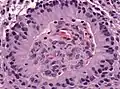

Периваскулярные псевдорозетки встречаются в большинстве эпендимом независимо от степени злокачественности или варианта. Они значительно более важны для диагностики эпендимомы, чем истинные эпендимальные розетки. Но к сожалению, периваскулярные псевдорозетки менее специфичны — они также встречаются в медуллобластомах, PNET, центральных нейроцитомах и, реже, в глиобластомах, а также в редких детских опухолях, мономорфных пиломиксоидных астроцитомах.[2]

Периваскулярные псевдорозетки в эпиндимоме

Эпендимальные псевдорозетки вокруг пролиферирующего эндотелия при анапластической эпендимоме